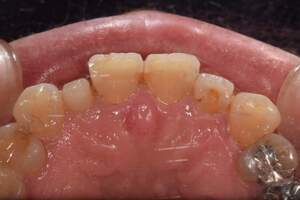

歯石除去

治療前1

治療後1

治療前2

治療後2

| 年齢 | 56歳・男性 |

|---|---|

| 主訴 | 主訴:歯石除去 治療部位:全顎 |

| 治療内容 | 初診検査・歯石除去 |

| 治療期間 | 60分 |

| 費用 | 合計約5,000円 初診検査約3,000〜4,000円 歯石除去約1,000円 (2024年4月現在) (歯の本数や検査内容で料金が変動します。) |

| リスク・副作用 | ・歯と歯の間に隙間ができるので、息が漏れ発音しにくいと感じることがあります。 ・歯ぐきの炎症がある場合は歯石除去中に出血を伴う可能性があります。 ・処置後に歯がしみることがあります。 ・歯ぐきの炎症が軽減すると歯ぐきが引き締まり、歯が長く見えることがあります。 |

| 治療方針 | 歯石除去・ブラッシング指導後SRP(歯ぐきの中に付着する歯石の除去) |

| 特記事項 | ・30年ぶりの歯科医院 ・毎食後の歯ブラシ習慣はあるが1分程度 |

| 担当者所見 | 全体の検査と歯石除去希望で来院されました。 特に下顎前歯部の歯と歯の間の歯石が、笑った時に見えてしまい気になるとのことで、初診検査後に歯石除去を行いました。 ブラッシング指導は歯間ブラシの入れ方と歯ブラシの動かし方をお伝えしました。 今後は治療と共に縁下歯石(歯ぐきの中に付着する歯石)の除去を行なっていく予定です。 |